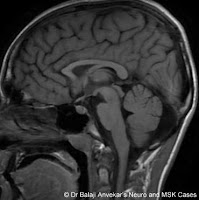

Ears of the lynx sign MRI Brain

- Ears of the lynx sign MRI Brain